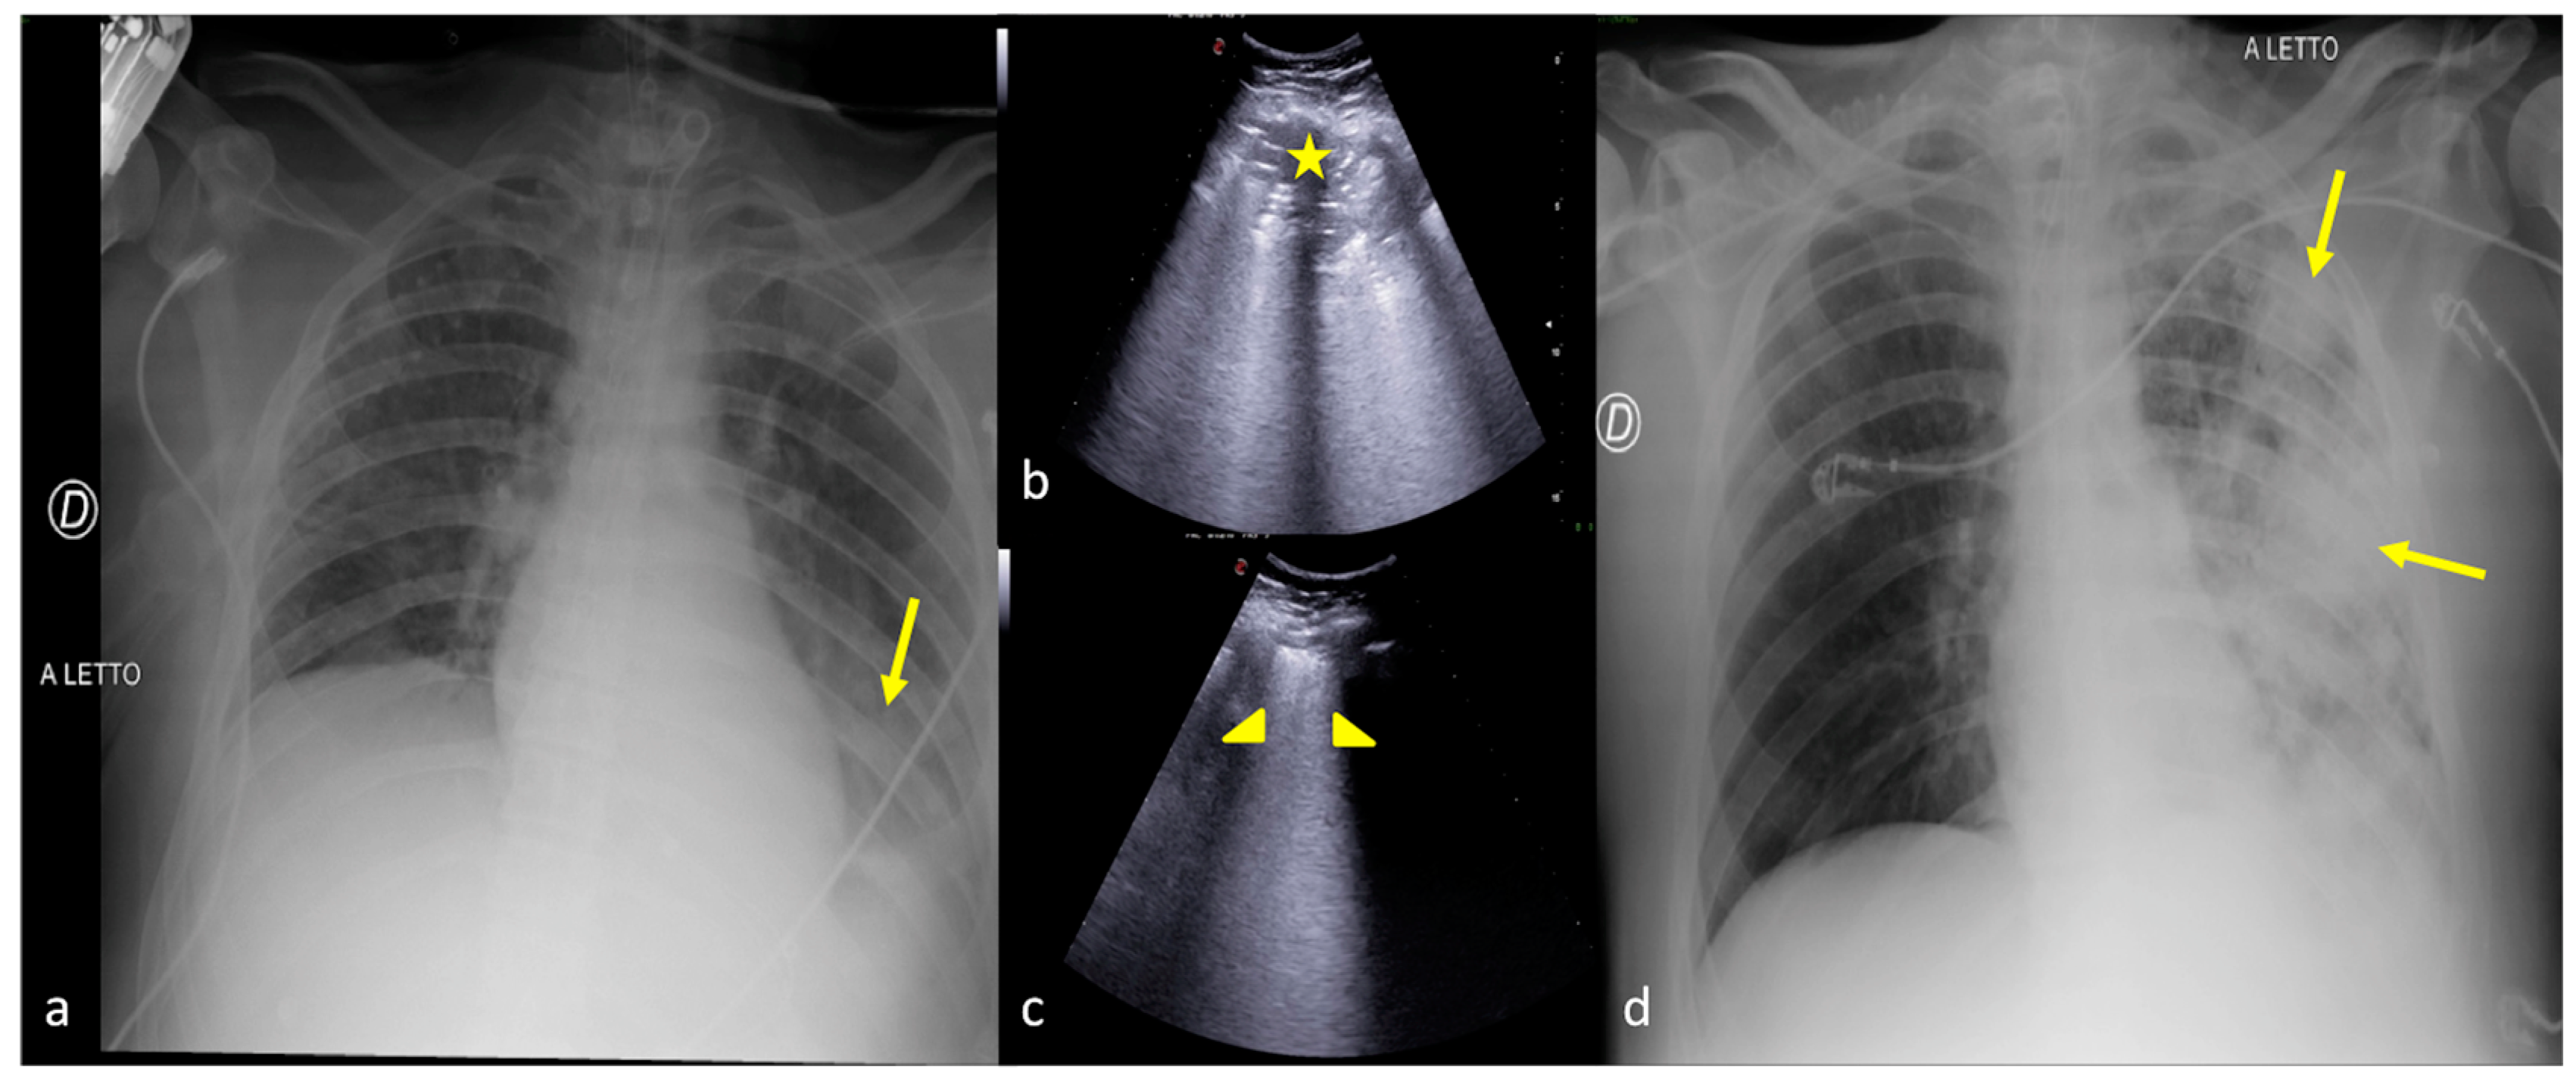

2.1. Atelectasis

2.2. Pneumonia

2.3. Pleural Effusion